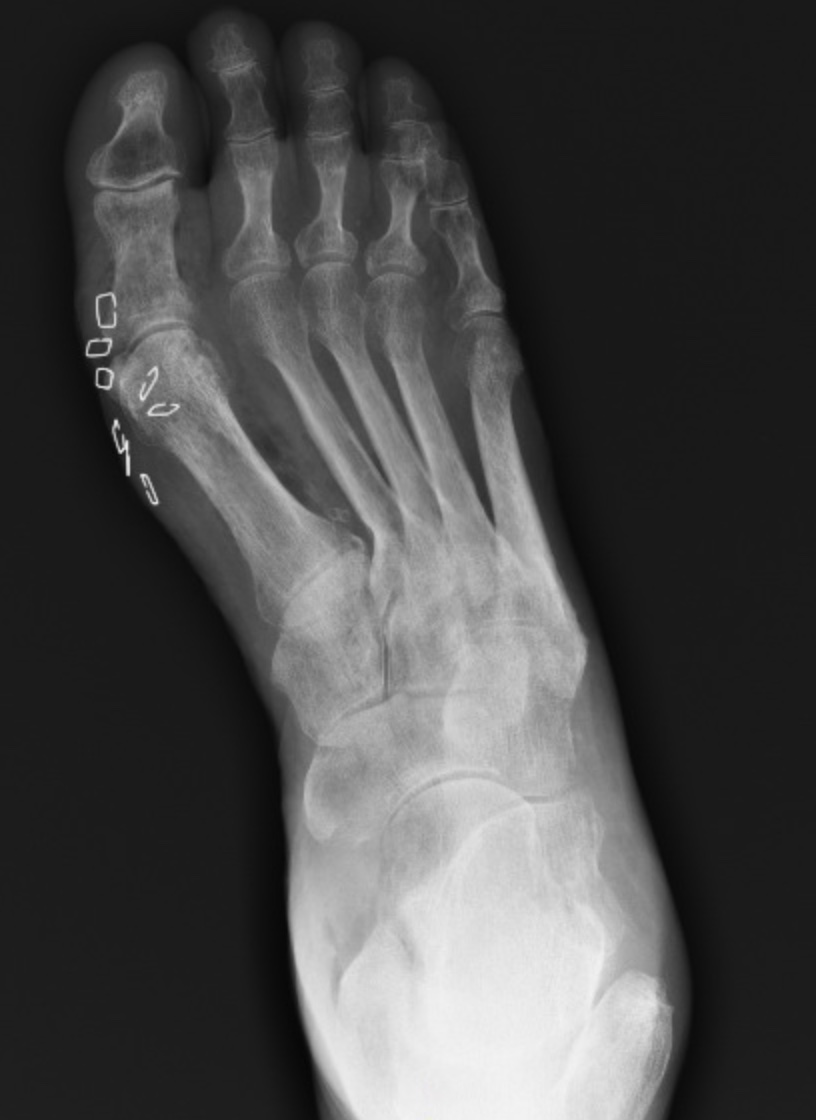

Answer: Gas gangrene

- gas on imaging (xray, CT, MRI)